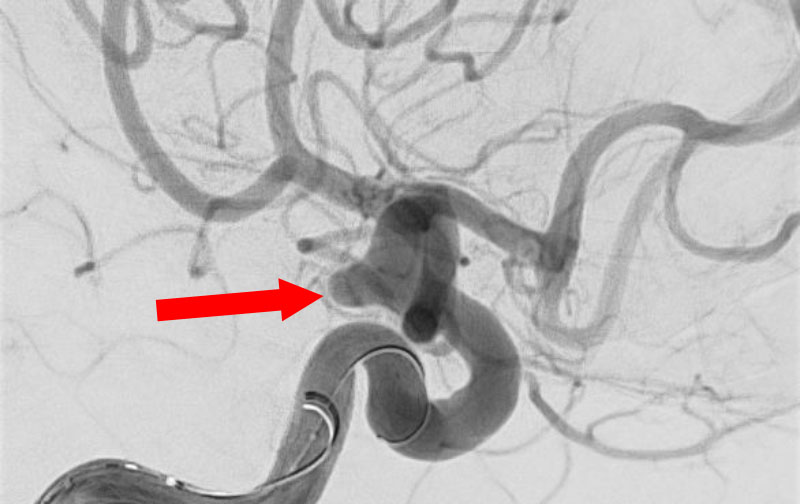

No.1595 手術中